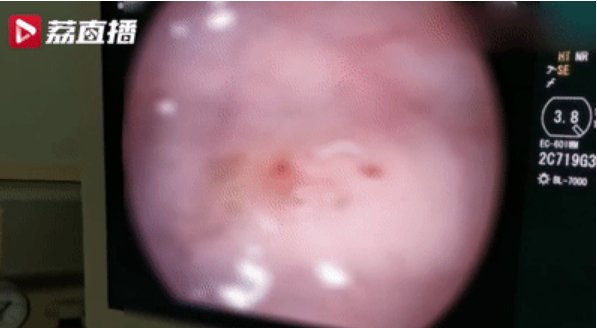

医生为小青进行胃肠镜检查,发现其肠腔内布满了多条活生生、正在蠕动的寄生虫!连医生都被吓到了,因为随便在一个镜头下面都看到有五六条虫,有的甚至咬住了肠粘膜,引起肠道损伤出血。